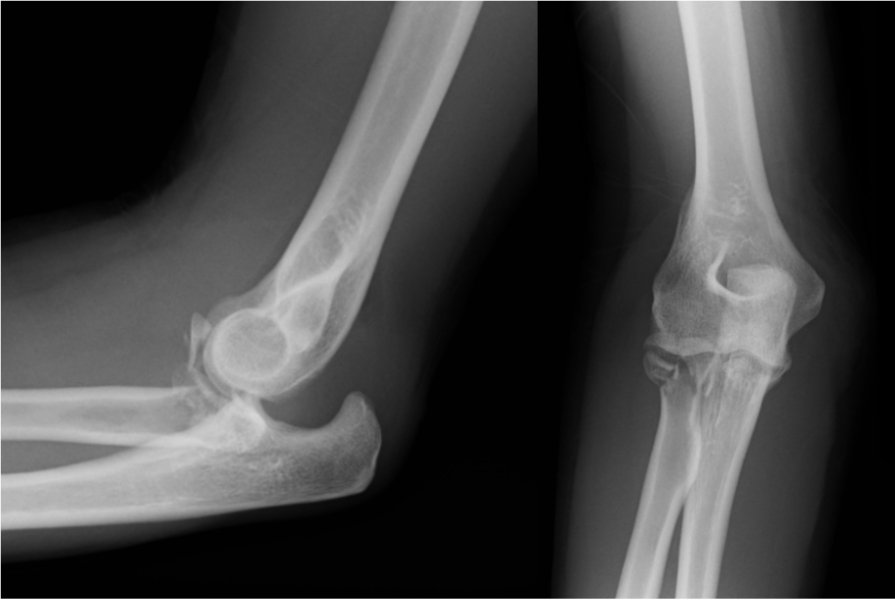

2a. Displaced fracture of the radial head with dislocation of the elbow